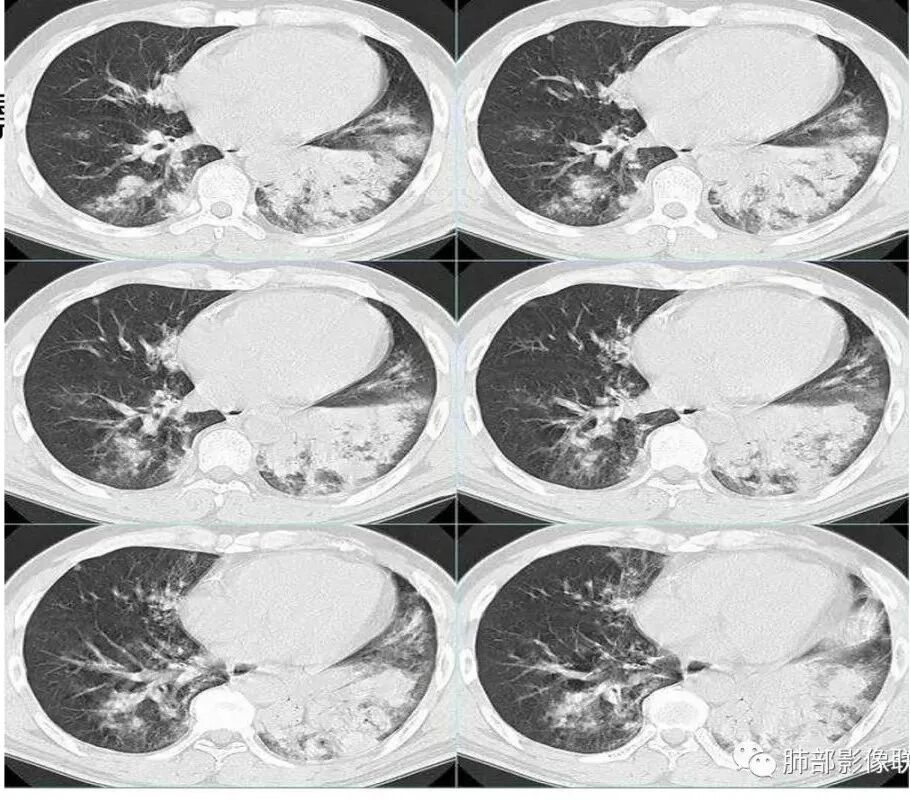

中年男性,咳嗽发热伴咳血胸痛。以左下肺大片实变混合磨玻璃为主,另两肺散在斑片状阴影,渗出明显边缘模糊,左下肺病灶部分边缘平直,病灶内未见明显空洞气囊等,未见树芽。纵隔窗显示病灶范围明显缩小提示渗出为主,双侧胸腔未见明显积液。首诊还是感染性病变,细菌,真菌,病毒,气道播散型金葡菌?非典型肺炎?

左肺实变膨胀感不强,未见枯树枝征,多发小叶改交,但不是支气管播散的腺泡结节,纵隔窗左下实变蜜度明显等于大于肌肉密度,粘液感不强,男性,病史短、有发热不支持粘液腺癌

男,52,咳嗽咳痰胸痛半月,近期加重,发热3天,声嘶伴气短1天,昨晚痰血。胸部CT:双肺多发斑片影、结节影,大小不一,密度不一,有GGO、有实性,沿支气管血管束分布,中内带多,边界不清,支气管进入,支气管充气征,似有小叶内间隔增厚,考虑:血管炎?肺水肿?鉴别感染、腺Ca、淋巴瘤等。

这个区域应该是外侧最重的,但是没有看到空洞。二元论也可以,单纯从影像看金葡也不一定都是小叶性改变的,肺泡性改变也可以,从病史看,可能病毒合并金葡。

就是说这个基础病变不知道是什么,肯定有基础病变,不然不符合,因为前上个星期才去讲这个金葡的,当时一看,这个斑片斑片确实有金葡的一些特点存在,支气管壁有增厚。

那我当时很诧异的就是这个,刚才说这个感染没有问题,恶性特征真没有,不符合,看到这个周围有一定的修复的迹象,这个特别诧异,怎么会是这样改变。

怀疑这个可能是在治疗过程中,改变了影像学表现。

这是气道早期金葡菌的特点